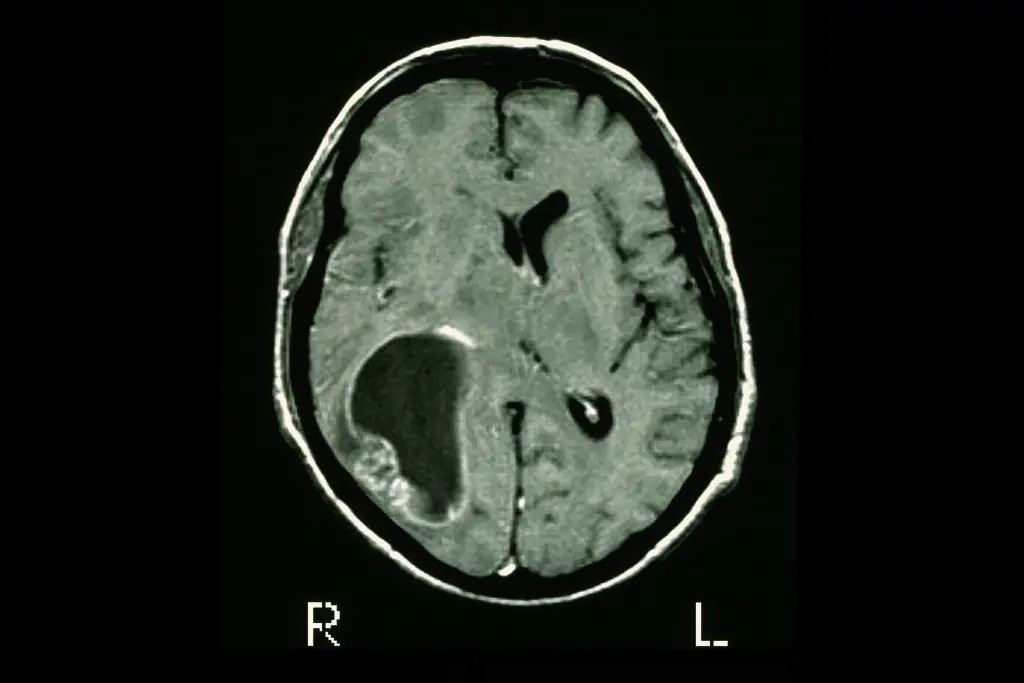

One of the patients, a 57-year-old woman, saw her cancer almost disappear in just five days after undergoing CAR-T therapy, with scans showing a dramatic reduction in the mass in her brain.

See the change on the brain scan below:

According to the new study, published in the New England Journal of Medicine, the woman saw "near-complete tumor regression" after just five days, while the other two patients also saw significant reductions in their tumors.